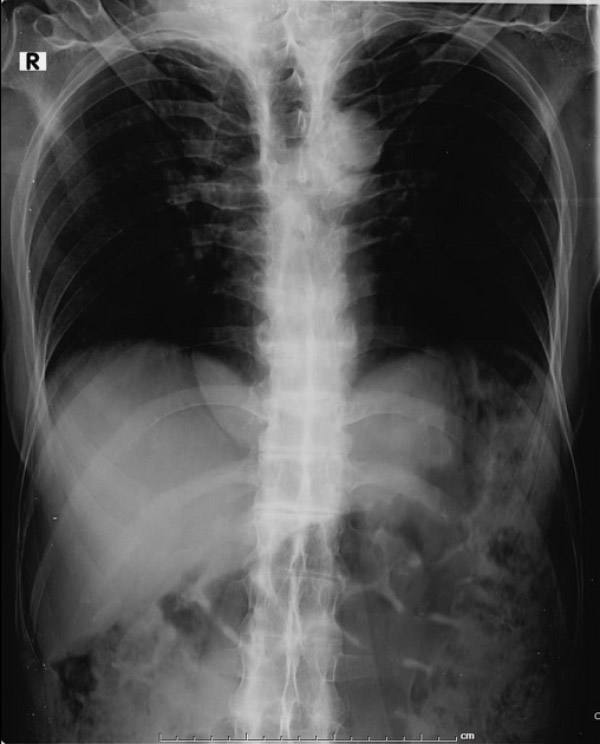

Chụp X-quang là phương pháp chẩn đoán hình ảnh viêm cột sống dính khớp được thực hiện đầu tiên giúp phát hiện các dấu hiệu viêm khớp cùng chậu, dính khớp cột sống và các thay đổi xương khác:

Hình ảnh X-quang viêm cột sống dính khớp có thể cho thấy các dấu hiệu như xói mòn xương, hình vuông hóa đốt sống, cầu xương (syndesmophytes) và dính khớp. Tuy nhiên, cần lưu ý rằng X-quang có độ nhạy hạn chế trong giai đoạn sớm của bệnh, khi các tổn thương viêm chưa gây ra thay đổi cấu trúc xương rõ ràng.

Sau đây là một số hình ảnh viêm cột sống dính khớp trên X-quang: